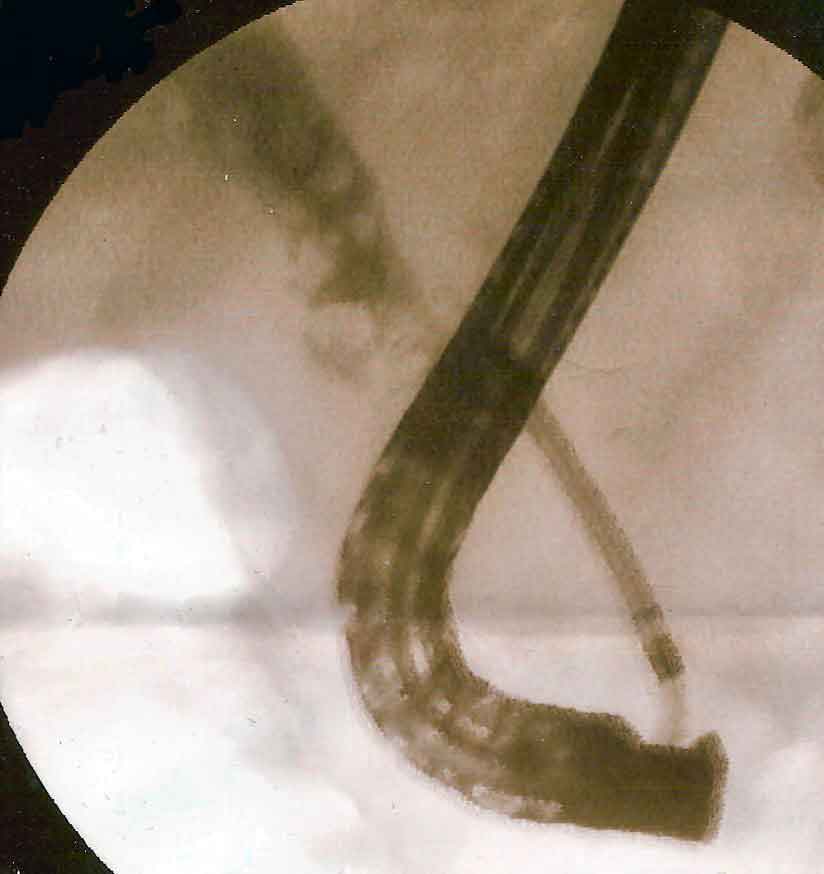

ERCP fluoroscopy showing stone extraction from the common bile duct

Therapeutic — Treat at Same Sitting

ERCP

Endoscopic Retrograde Cholangiopancreatography. Primarily a treatment procedure for CBD stones, jaundice, and cholangitis. An endoscope enters the bile duct opening; stones are removed and stents placed. Also provides precise duct imaging at the same sitting.